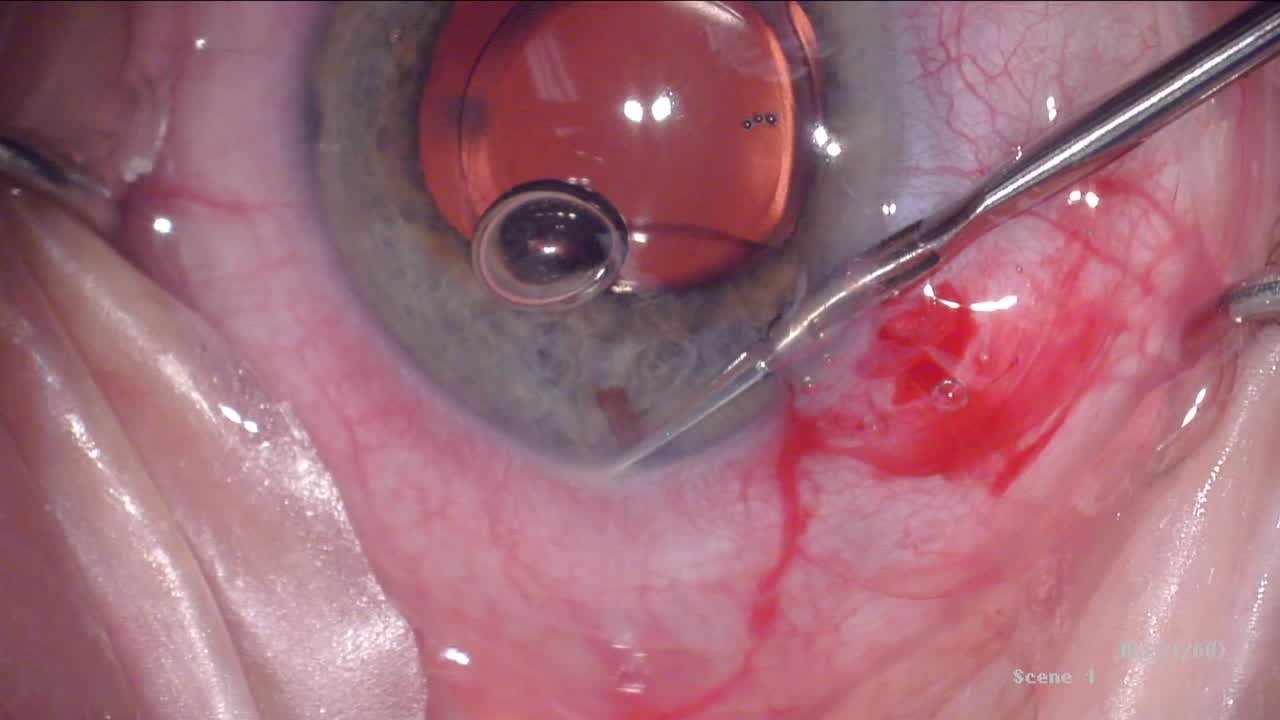

iDose TR® Live Procedure Broadcast

John Berdahl, MD; Iqbal Ike K. Ahmed, MD, FRCSC; Lorraine M. Provencher, MD; and Savak Teymoorian, MD, MBA

Live Demonstration: iDose TR® Implantation